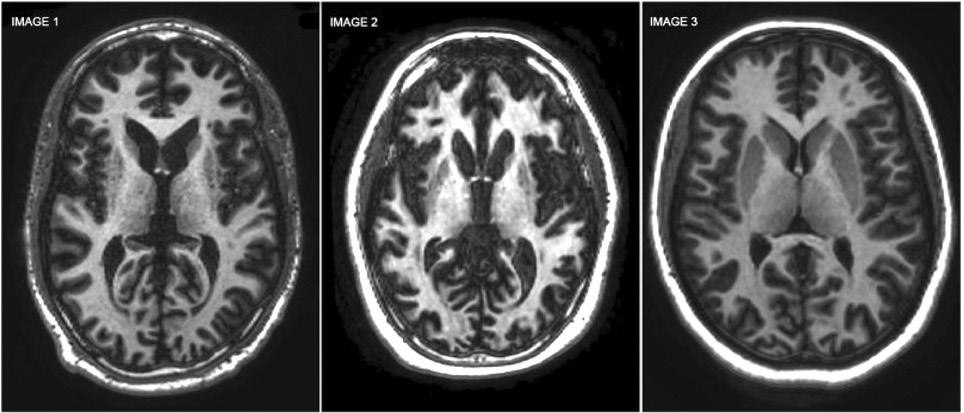

CT scans that display the presence of Huntington’s disease in the brain.

A series of CT scans that display the presence of Huntington’s disease in the brain

and intensify as time goes on. Early symptoms can be personality changes, confusion and memory loss or chorea (involuntary twitches or muscle spasms). Chorea comes from the Greek word to dance as the movements can be unexpectedly big. These regions are responsible for cognitive functions, learning and motor skills, the execution of movement as well as our memory and emotions.

AMT-130 is the new gene therapy that has been designed to slow the progression of HD. The treatment was developed by uniQure, a company specialising in gene therapies for severe and rare genetic diseases. This therapy is injected into the putamen and caudate nucleus, deep in the centre of the brain, with the aid of magnetic resonance imaging (MRI). This operation takes up to ten hours as the surgeons carefully deliver AMT-130 three separate times.

The results of UniQure’s trial showed that after around three years, there was an average 75% slowing of the disease progression. This data was collected via MRI scans and studies of the protein levels in the fluid around the brain. It shows that AMT-130 stops brain neurons from dying. However, these results do not have longer term outcomes; positive or negative. It could be that AMT-130 solves more problems than we thought, or it could create unforeseeable problems down the line.